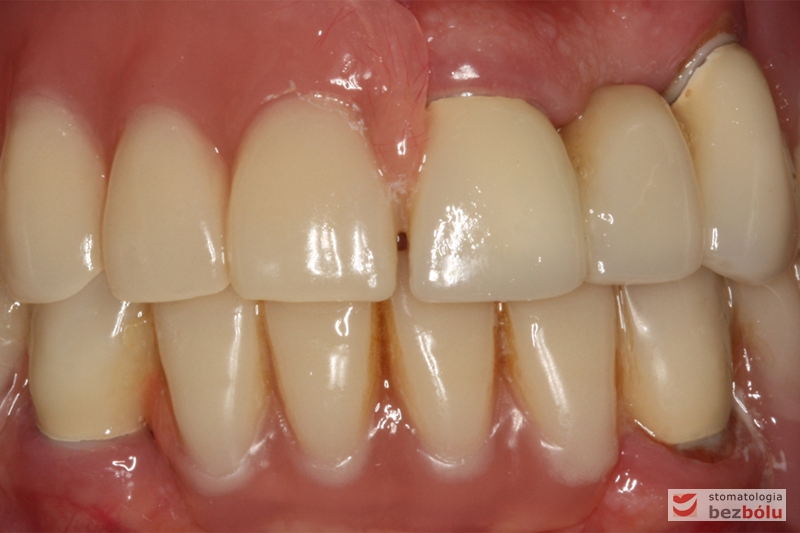

Ostateczny efekt terapeutyczny - zadowolona i uśmiechnięta pacjentka

Ostateczny efekt terapeutyczny – zadowolona i uśmiechnięta pacjentka